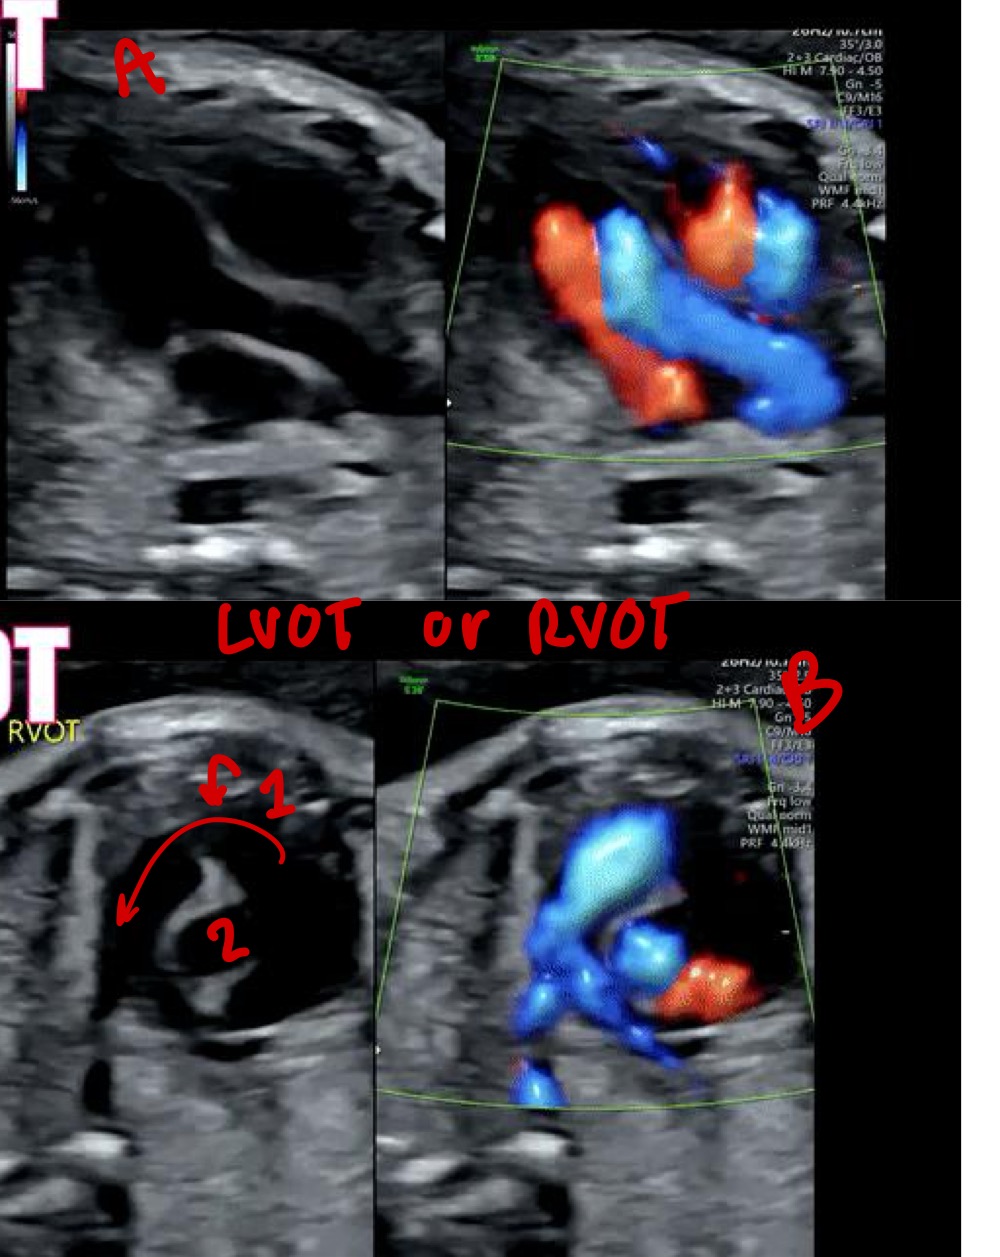

What does LVOT stand for

Left ventricular outflow tract

What vessel arises from the left ventricle in LVOT

Aorta

What is the "ballerina foot" sign associated with

LVOT view

What abnormality can be assessed in LVOT

Ventricular septal defect (VSD)

Right ventricle

Left atrium

Left ventricle

What does RVOT stand for

Right ventricular outflow tract

What vessel arises from the right ventricle

Pulmonary artery

A= LVOT

B= RVOT